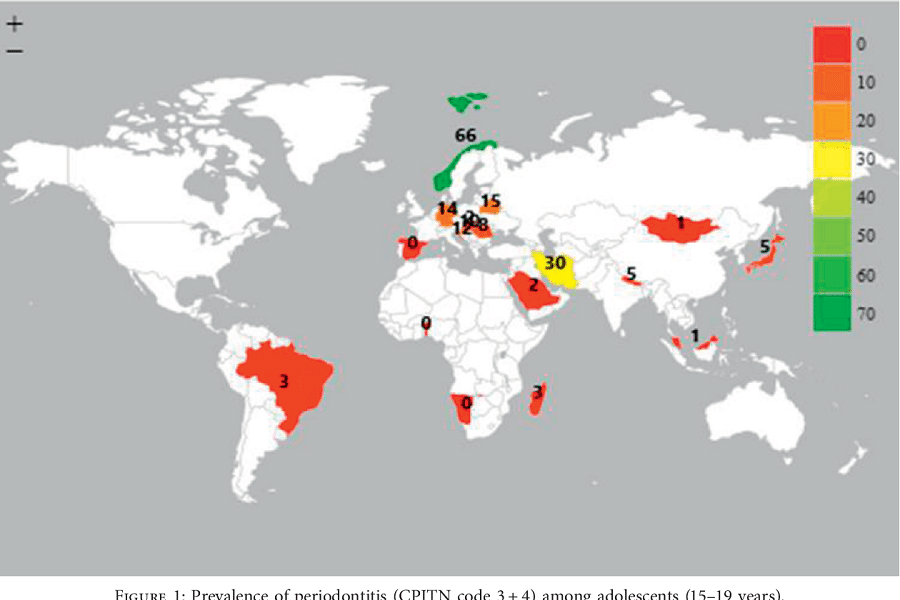

Μεγάλος αριθμός ανθρώπων δεν έχει πρόσβαση στην πρόληψη και τη θεραπεία των οδοντοστοματικών ασθενειών Ο Παγκόσμιος Οργανισμός Υγείας έχει καταρτίσει πλήρη πίνακα της κατάστασης σε 194 χώρες και αποκαλύπτει αύξηση κατά 1 δισεκατομμύριο περιστατικών κατά τα τελευταία 30 χρόνια. «Πρόκειται για μία σαφή ένδειξη ότι μεγάλος αριθμός ανθρώπων δεν έχει πρόσβαση στην πρόληψη και την θεραπεία των οδοντοστοματικών ασθενειών», αναφέρεται στην έκθεση του ΠΟΥ που αναδεικνύει ως συνηθέστερα τα περιστατικά των χαλασμένων δοντιών, των ασθενειών των ούλων και των καρκίνων του στόματος. Η φθορά των δοντιών είναι το συχνότερο περιστατικό. Αφορά 2,5 δισεκατομμύρια άτομα στον κόσμο, ενώ ένα δισεκατομμύριο πάσχει από ασθένειες των ούλων που είναι και η βασική αιτία για την απώλεια των δοντιών. Ταυτόχρονα, 380.000 νέα περιστατικά καρκίνου του στόματος διαγιγνώσκονται κάθε χρόνο. Οι βασικοί παράγοντες κινδύνου είναι η μεγάλη κατανάλωση ζάχαρης, η χρήση καπνού και η κατανάλωση αλκοόλ. Ο Παγκόσμιος Οργανισμός Υγείας καλεί τις αρχές να αντιμετωπίσουν τους παράγοντες κινδύνου προωθώντας μία διατροφή ισορροπημένη και χαμηλή σε σάκχαρα, τη διακοπή χρήσης καπνού υπό οποιαδήποτε μορφή, την ελάττωση της κατανάλωσης αλκοόλ και τη μεγαλύτερη πρόσβαση σε αποτελεσματικές και προσιτές φθοριούχες οδοντόκρεμες.